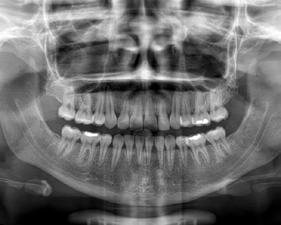

b) Análisis radiográficos, periapicales, ortopantomográficos, oclusales, lateral de cráneo, anteroposterior de cráneo.

c) Estudio y análisis tomográfico en tercera dimensión del cráneo a nivel maxilar y mandibular (Figura 24).

24.

Figura

1. La existencia y presencia de todos los elementos anatómicos craneodentofaciales (Figura 26).

3. Los desplazamientos óseos, como consecuencia de su crecimiento endocondral o intramembranoso en las diferentes zonas o áreas de remodelación, aposición y reabsorción (Figura 27).

Todos los cambios dimensionales de los huesos faciales y su consecuente movimiento y remodelación, están íntimamente relacionados con los estímulos fisiológicos que activan las matrices funcionales de crecimiento, por la presencia de todos los elementos anatómicos (como los caninos), de manera adecuada, en coordinación con los demás elementos que conforman el sistema estomatognático y el sistema respiratorio35,36 (Figura 28).

Al estar ausente algún germen dental (como los laterales superiores permanentes y/o premolares de ambas arcadas, “los de mayor incidencia”),10 se inhibe la estimulación adecuada en el desarrollo óseo de esa zona específica, ya que al no existir el germen dental, la matriz ósea inhibe su crecimiento en esas zonas en específico11 (Figura 29).

maxilomandibulares, 17 las cuales propician alteraciones en el proceso del intercambio dentario; en la que una reducción de los espacios necesarios para el acomodo de los caninos y de otros órganos dentales en las arcadas, retrasa e impide que el impulso natural propio de la formación radicular como empuje fisiológico, impidiendo el desplazamiento y la erupción del canino en tiempo y una posición ideal dentro del arco dental (Figura 30).

Sumado a lo anterior, la retención generada dentro del macizo óseo basal altera su posición en angulación y dirección correcta de erupción. Situación que en ocasiones daña las raíces de los dientes adyacentes al canino y que finalmente podrá quedar incluido, en el peor de los casos, cuando no encuentra una salida de emergencia hacia el paladar o el vestíbulo12 (Figura 31).

consideraciones a tomar muy en cuenta como factor etiológico en la inclusión del canino (Figura 32).

Por otro lado, al haber una pérdida prematura de un diente deciduo, además de generar una disminución de la longitud del arco dental, la biomecánica fisiológica propia de nuestro organismo, tiende a cerrar los espacios o brechas generadas por la pérdida de algún órgano dental, mesializando los dientes distales al diente faltante y generando extrusión del antagonista inmediato (Figura 33).

Figura 29.

Figura 30.

Figura 31.

Figura 32.

Alteraciones faciales

Todos los dientes intervienen en la conformación de una oclusión ideal, así como del volumen facial en el tercio medio e inferior de la cara. Es el caso, que la presencia del canino superior permanente en la arcada en el tiempo cronológico adecuado, es muy importante para el desarrollo óseo del tercio medio facial, ya que estimula el crecimiento del maxilar tanto en el área lateral del ala de la nariz bilateralmente, como en la pared anterior del macizo óseo, lo cual, evita el hundimiento facial de la parte inferior del pómulo y la rectificación facial de los músculos en esta área15 (Figura 34).

tercio inferior, al coordinarse con los caninos superiores en todos los movimientos fisiológicos, como la masticación18 (Figura 35).

El desarrollo y crecimiento mandibular a nivel de la rama, cuerpo y parte anterior en la zona del mentón, depende en parte de la presencia del canino, para efectuar correctamente los movimientos esenciales de lateralidad, protrusión, cierre adecuado de la mordida, además de armonizar el desarrollo correcto de la curva en la arcada dental en el plano transversal o de Wilson, así como de la curva sagital anteroposterior o de Spee19,20 (Figura 36).

La dinámica muscular

Figura 33.

Figura 34.

Figura 35.

Figura 36.

4. Los tiempos biológicos en el cierre de crecimiento óseo39 (Figura 38).

Otra consideración a valorar, son los malos hábitos, entre los que se encuentran con más frecuencia los deletereos y que recaen en la mayoría de las complicaciones para la erupción de los caninos. El tiempo, perseverancia, permanencia e intensidad de estos malos hábitos será proporcional a las alteraciones óseas que se generen, parafunciones musculares y respiratorias, desplazamientos dentales y la consecuente maloclusión presente al momento de realizar el diagnóstico definitivo previo al plan de tratamiento22 (Figura 39).

El colapso bilateral en el maxilar es una de las consecuencias más frecuentes de estos malos hábitos y por consiguiente, propicia una reducción en las dimensiones perimetrales del paladar y del arco dental, aumentando la profundización de la bóveda palatina, generando complicaciones a nivel respiratorio entre otras complicaciones, dando resultados no favorables como la respiración bucal,

acomodo no fisiológico lingual, etc.; lo cual, refleja un acompañamiento del subdesarrollo en el cuerpo y rama mandibular, el cual es un factor crítico para el acomodo de los caninos en la etapa del intercambio dental23 (Figura 40).

Figura 37.

Figura 38.

Figura 39.

Figura 40.

1. Arco extraoral, el cual pude ser utilizado con tracción alta, media o cervical.40,41 Péndulo o aparato de Hillgers modificado (Figura 41).

2. Mascara facial (Figura 42).

3. Bionator simple o combinado con lip bumper, entre otros (Figura 43).

Figura 41.

Figura 42.

posicionada en dirección vestibular, ya que solamente el 17% de caninos impactados vestibularmente tienen un espacio suficiente, a comparación de los impactados donde la corona tomó la dirección hacia el paladar, ya que por lo regular en estos casos, el canino deciduo siguió estando presente sin reabsorción alguna, el cual desempeña un papel importante como mantenedor de espacio biológico; sin embargo, genera la necesidad de que el canino busque una salida emergente, que en estos casos es hacia la bóveda palatina44 (Figura 44).

Está indicada cuando el canino está en una posición infraósea, muy apical al plano oclusal y por arriba de la línea mucogingival. Se remueve el tejido óseo palatino que cubre la corona, colocando un apósito quirúrgico, evitando la formación de tejido mucoso, logrando que el diente erupcione por sí mismo46 (Figura 45).

Esta técnica es la más sugerida cuando el canino se encuentre submucoso y alejado del plano oclusal y los resultados a nivel periodontal y estético tengan un mejor pronóstico.47,48

A partir de la realización de un colgajo, se retira en caso de ser necesario, el hueso que cubre la corona del canino, colocando un aditamento que permita traccionar al diente incluido, cuando el periodo de cicatrización haya concluido. Paso seguido se colocarán los aditamentos de

anclaje para movilizar de forma controlada en fuerza y dirección correcta al canino incluido hacia el arco dental.

Figura 45.